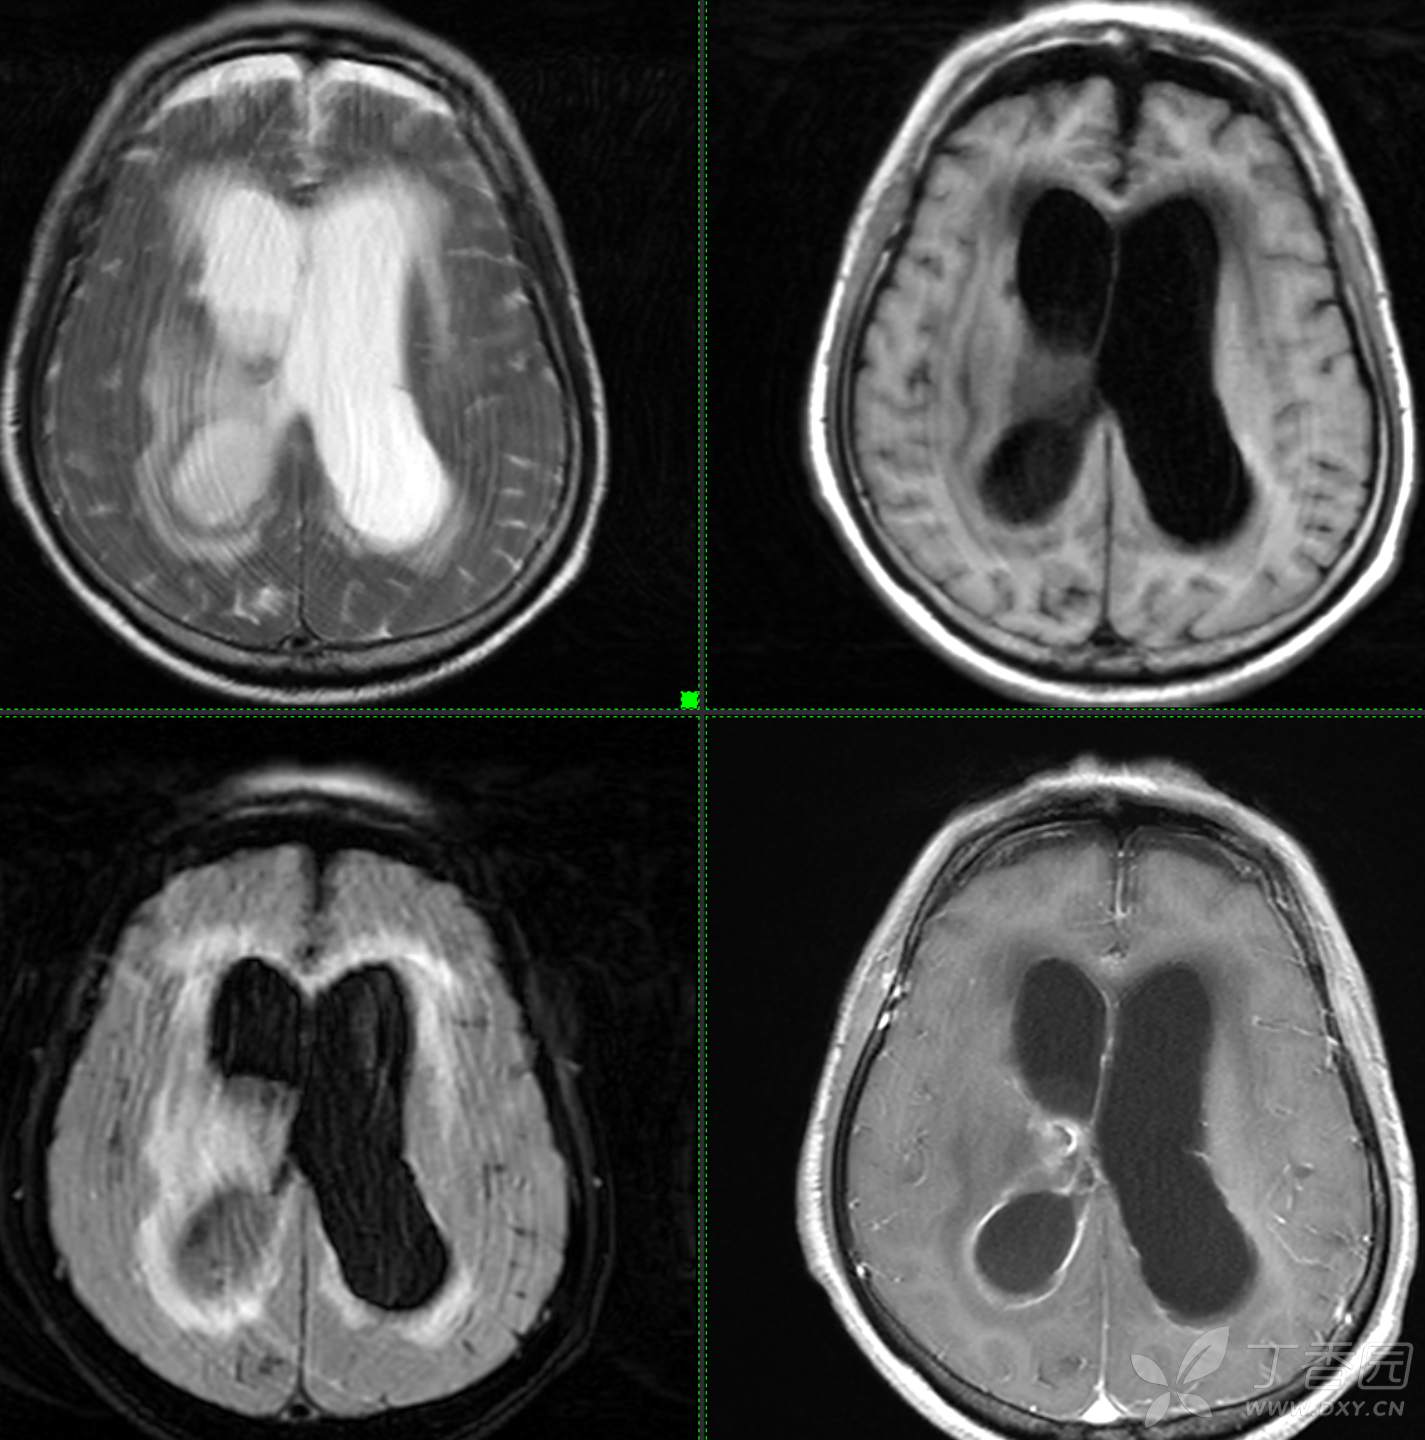

现病史: 患者3周前无明显诱因下出现头晕,无头痛,伴视物模糊,肢体乏力,走路步态不 稳,无意识不清,对答切题,当地医院查血常规示:中性粒细胞分类:77.7%.淋巴细胞分类:15.6%,中性性粒细胞分类:7.1*10^9/L.葡萄糖:22.35mmol/,头颅平扫示:右侧丘脑饱满,密度减低伴低密度灶,占位不排除,两侧半卵圆区、额叶低密度灶,以“1.糖尿病酮症酸中毒,2.颅内占位性病变”收入住院治疗,1周前住院期间出现发热,先后予抗感染,控制血糖等对症支持治疗,2天前无明显诱因下再次出现发热,伴血糖升高,自测体温40℃,血糖20mmol儿,伴气促无胸闷,袖志模糊,反应迟钝,无畏寒寒战,无腹痛腹泻等不适,昨日送至我院就诊